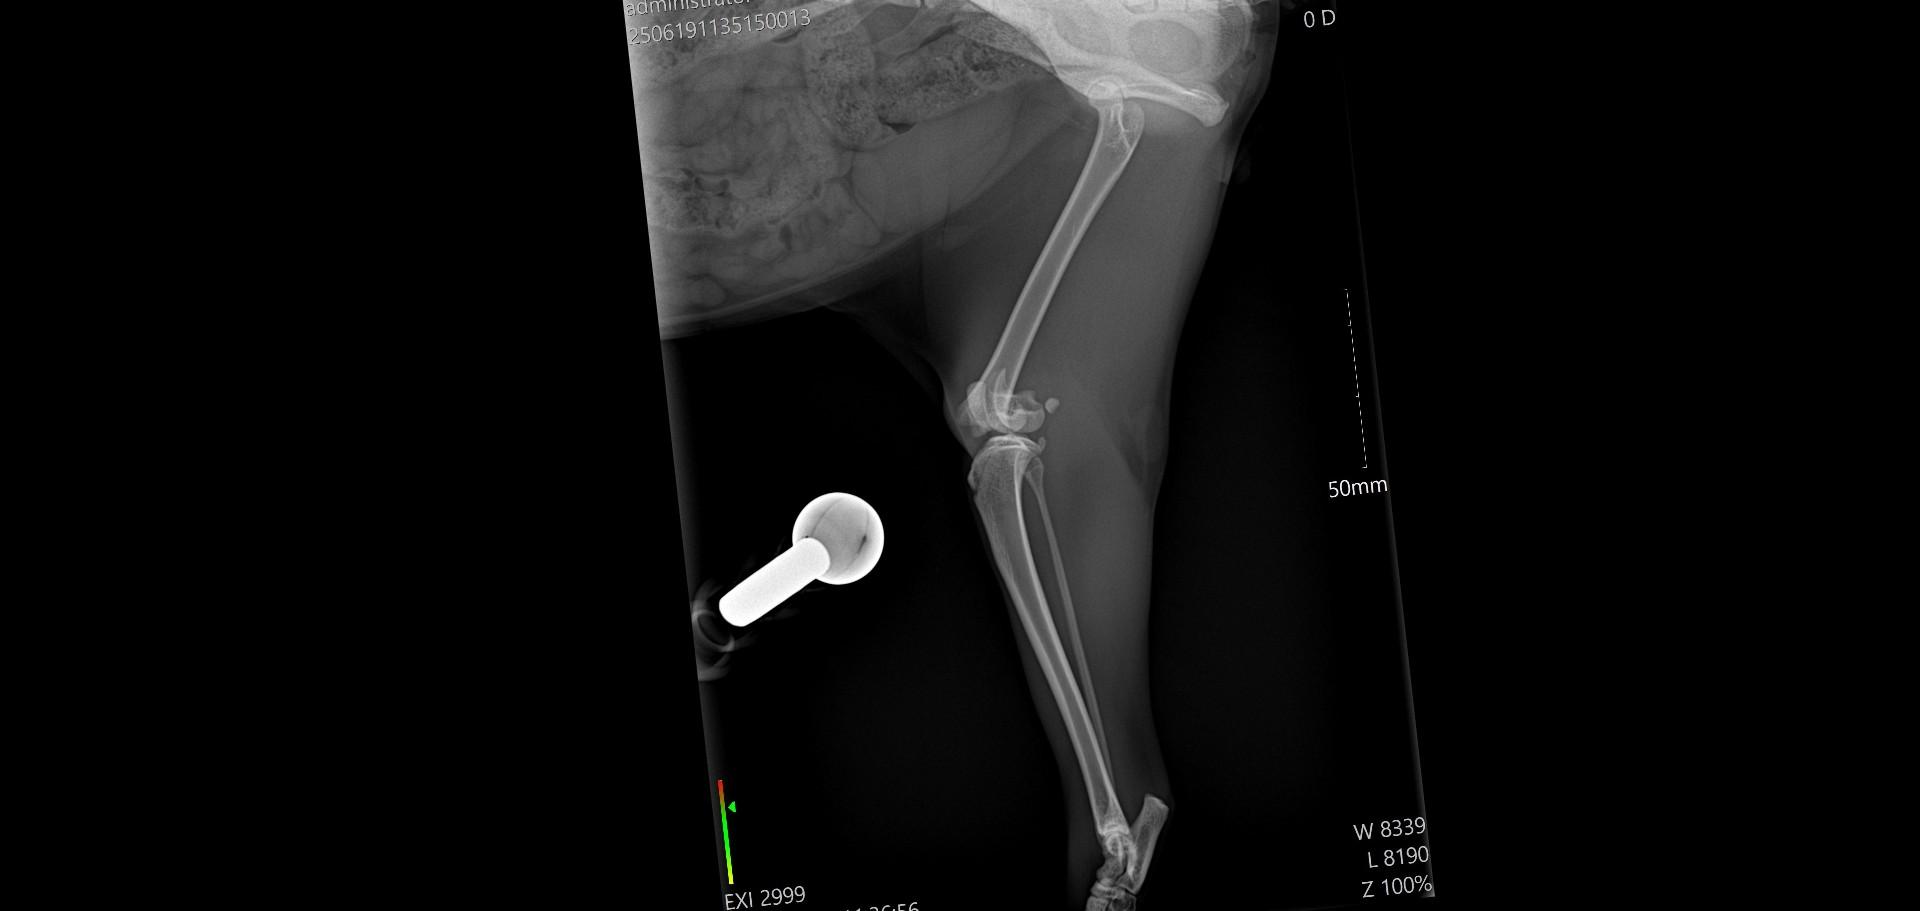

Dnes ráno měl  být Merlinek propuštěn do domácího léčení, bohužel jeho stav po narkóze neodpovídal běžnému stavu a musel ještě zůstat na klinice. Zítra budeme vědět víc a doufáme, že bude už v pořádku a pojede s námi domů, kde má vše připraveno na doléčení. Přikládáme snímky z rentgenu operované nožky. Děkujeme všem za podporu a pomoc s úhradu nákladů na operaci a hospitalizaci, které budou vysoké, bez vaší pomoci bychom to nezvládli.